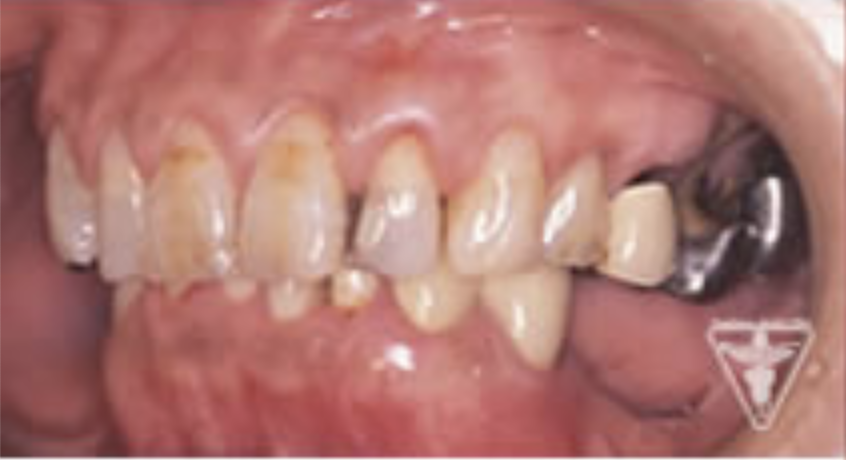

治療前

下の奥歯が左右なくなっており、かみ合わせが深くなっています。

顎のずれは認めませんが、歯肉が厚く中に炎症を取りこみやすいタイプの歯肉です。

左の顎の骨が大きく溶けてなくなっております。